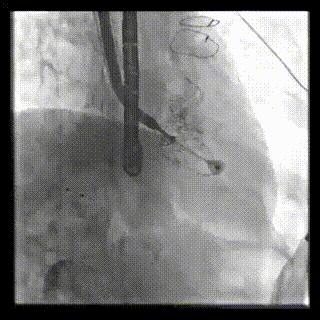

2021年12月24日,復(fù)旦大學(xué)附屬中山醫(yī)院葛均波院士團(tuán)隊(duì)成功應(yīng)用LuX-Valve Plus為一例極重度三尖瓣反流(TR)合并房顫、房缺的患者完成了經(jīng)血管三尖瓣置換術(shù),這是在前基礎(chǔ)上,本周完成的第三例經(jīng)血管三尖瓣置換手術(shù),葛均波院士、周達(dá)新教授等與心外科魏來(lái)教授、賴顥教授,心超室的潘翠珍教授、李偉教授及麻醉科的郭克芳教授共同完成了本周手術(shù),均獲得圓滿成功!患者術(shù)后超聲顯示無(wú)TR,臨床癥狀明顯改善。本周手術(shù)的成功也為L(zhǎng)uX-Valve Plus救治性臨床研究添上了濃墨重彩的一筆。

本周三例接受LuX-Valve Plus經(jīng)血管三尖瓣置換術(shù)的患者中,第一例患者為冠狀動(dòng)脈旁路移植術(shù)+Bentall+二尖瓣成形術(shù)后;第二例患者為永久起搏器植入術(shù)后,存在跨三尖瓣導(dǎo)線;第三例患者合并房顫、房缺及左心耳封堵術(shù)后。

三例患者入院后,葛均波院士團(tuán)隊(duì)周達(dá)新教授、潘文志教授、張?jiān)床┦?、陳莎莎博士及心超室的潘翠珍教授、李偉教授?duì)患者的情況進(jìn)行詳細(xì)評(píng)估和討論,最終決定為三例患者選擇LuX-Valve Plus40mm、50mm和50mm型號(hào)的瓣膜進(jìn)行手術(shù)治療。手術(shù)后即刻拔除氣管插管,術(shù)后患者三尖瓣反流癥狀得到顯著改善,復(fù)查心超結(jié)果顯示人工三尖瓣瓣膜支架固定穩(wěn)定,瓣葉關(guān)閉形態(tài)未見異常,未見明顯反流。